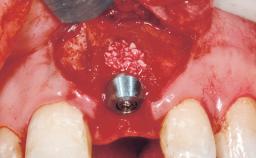

Immediate Flapless Placement of an Implant in a Maxillary Left Central Incisor Site

A 29-year-old female patient presented for treatment to replace the upper left central incisor tooth with an implant- supported restoration. The tooth had been intermittently symptomatic for the previous 12 months. The tooth had originally suffered trauma about 15 years previously. Several endodontic treatments had been performed, including an apicectomy procedure to retain the tooth. The patient was healthy and a non-smoker. She had reasonable expectations in regard to esthetic outcomes and the risk of marginal tissue recession following treatment. At medium smile, the gingival margins of the upper teeth were visible, with a display of 3 to 4 mm of the gingival margins. Gingival recession of tooth 21 and a discrepancy in the gingival levels between teeth 11 and 21 was observable during normal speech and smile.

Type of Implants One-Piece

Placement Protocol Immediate implant placement

Tooth Site Maxillary incisor or canine

Socket Morphology Single-root socket